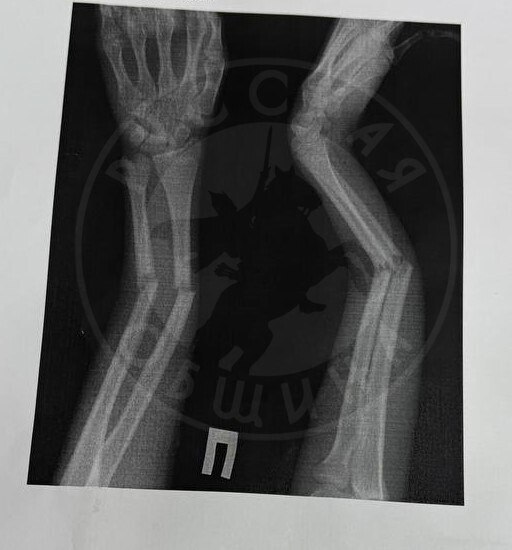

Выглядит это так: я пытаюсь собрать пальцы на обеих руках. С левой нет проблем, а правая - вот:

Пальцы не свести, и, в итоге, что-то делать даже рабочими пальцами стало крайне сложно. Минус клавиатура, минус мышка. Минус иголка и минус ручка. Минус ножик и отвёртка. Да много чего минус надолго. Только я начала было пользоваться правой рукой - и снова приехали, даже ложка опять вываливается.